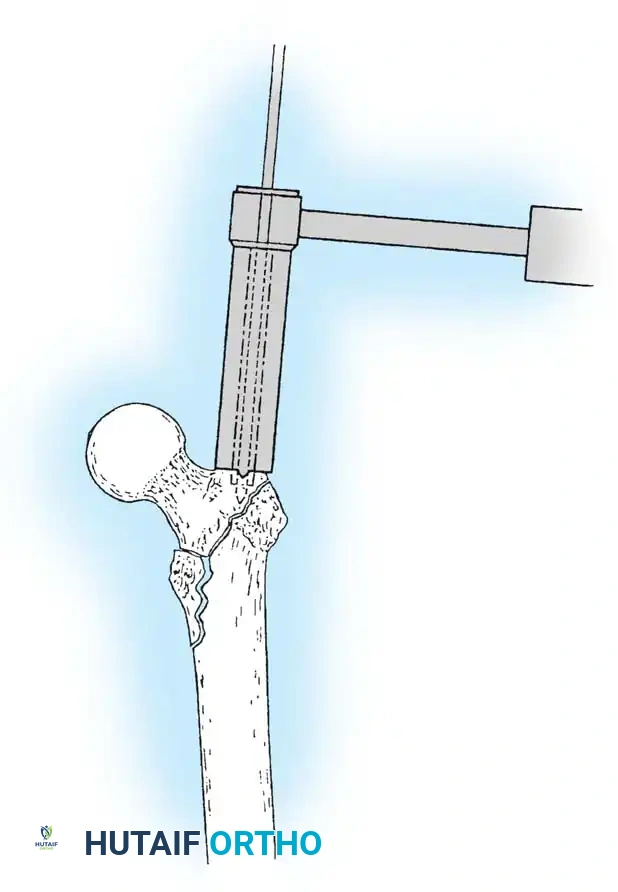

3. Guide Wire Placement

Whether using an SHS or a CMN, accurate placement of the guide wire into the femoral head is the most critical step of the operation.

Insertion of the guide wire. The wire must be positioned centrally in the femoral head on both AP and lateral views.

The Tip-Apex Distance (TAD):

Described by Baumgaertner, the TAD is the sum of the distance from the tip of the lag screw to the apex of the femoral head on both the AP and lateral radiographs. A TAD of less than 25 mm is strongly predictive of successful fixation; a TAD > 25 mm significantly increases the risk of screw cut-out.

4. Reaming and Lag Screw Insertion

Once the guide wire is perfectly positioned, the lateral cortex is opened, and the femoral neck is reamed over the wire.

Reaming of the femoral neck and head over the precisely placed guide wire, preparing the channel for the lag screw.

The lag screw is then inserted. It is crucial not to over-insert the screw, which can penetrate the articular cartilage, nor to under-insert it, which compromises fixation.